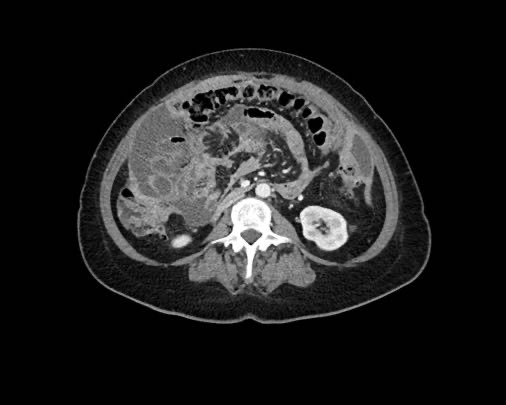

Rãnh cạnh đại tràng

Bất kỳ vị trí nào trong ổ bụng được phủ bởi phúc mạc đều có thể là đích đến của các nốt cấy ghép phúc mạc.

Các vị trí điển hình khác bao gồm rãnh cạnh đại tràng, túi cùng trực tràng-bàng quang hoặc trực tràng-tử cung, dây chằng liềm và mặt bụng của cơ hoành.